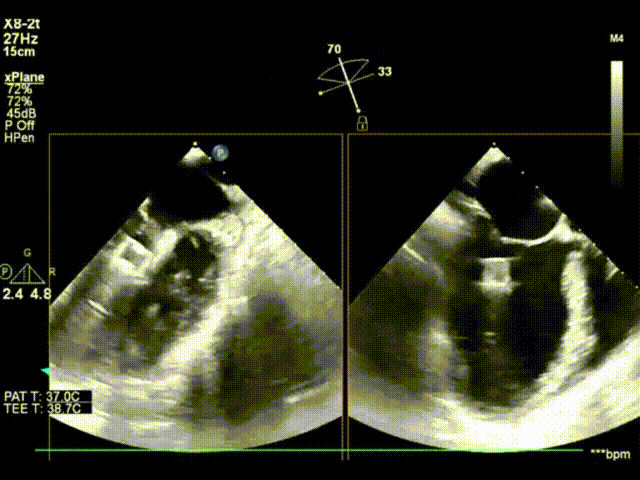

X-plane及3D模式外科视角下,跨瓣器顺利跨瓣,第二个ValveClamp夹合器上下夹定位夹合